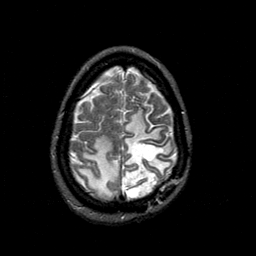

MR Study #1 -- Slice #42